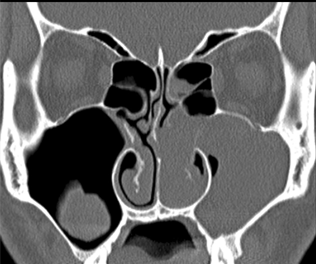

图:鼻息肉

图:鼻息肉CT